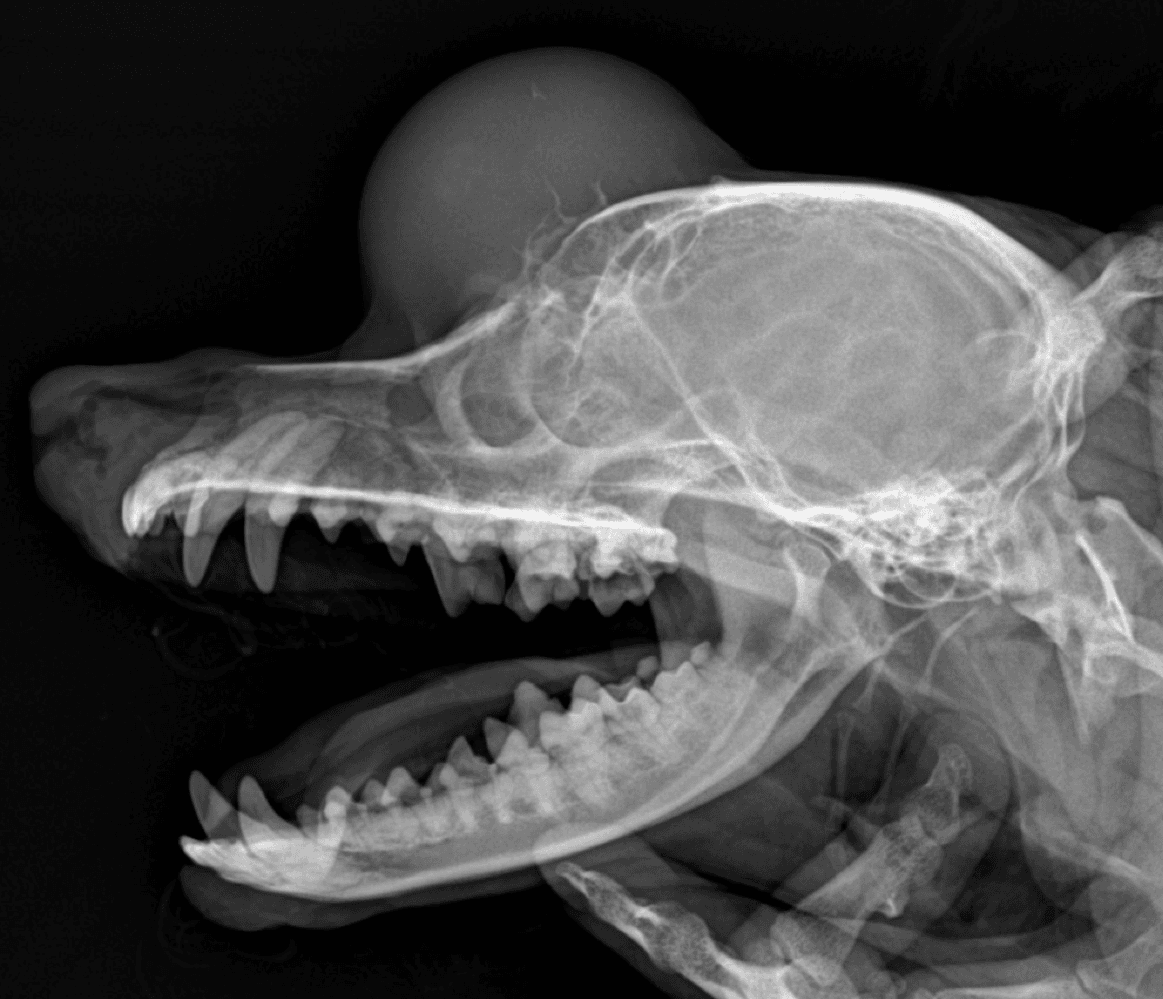

14스케일링,폴리싱 등의 치과치료시 짧은 마취시간으로 경제적 진료 가능

15치과 진단 및 치료시,육안으로 보이지 않는 치아상태 검진이 가능